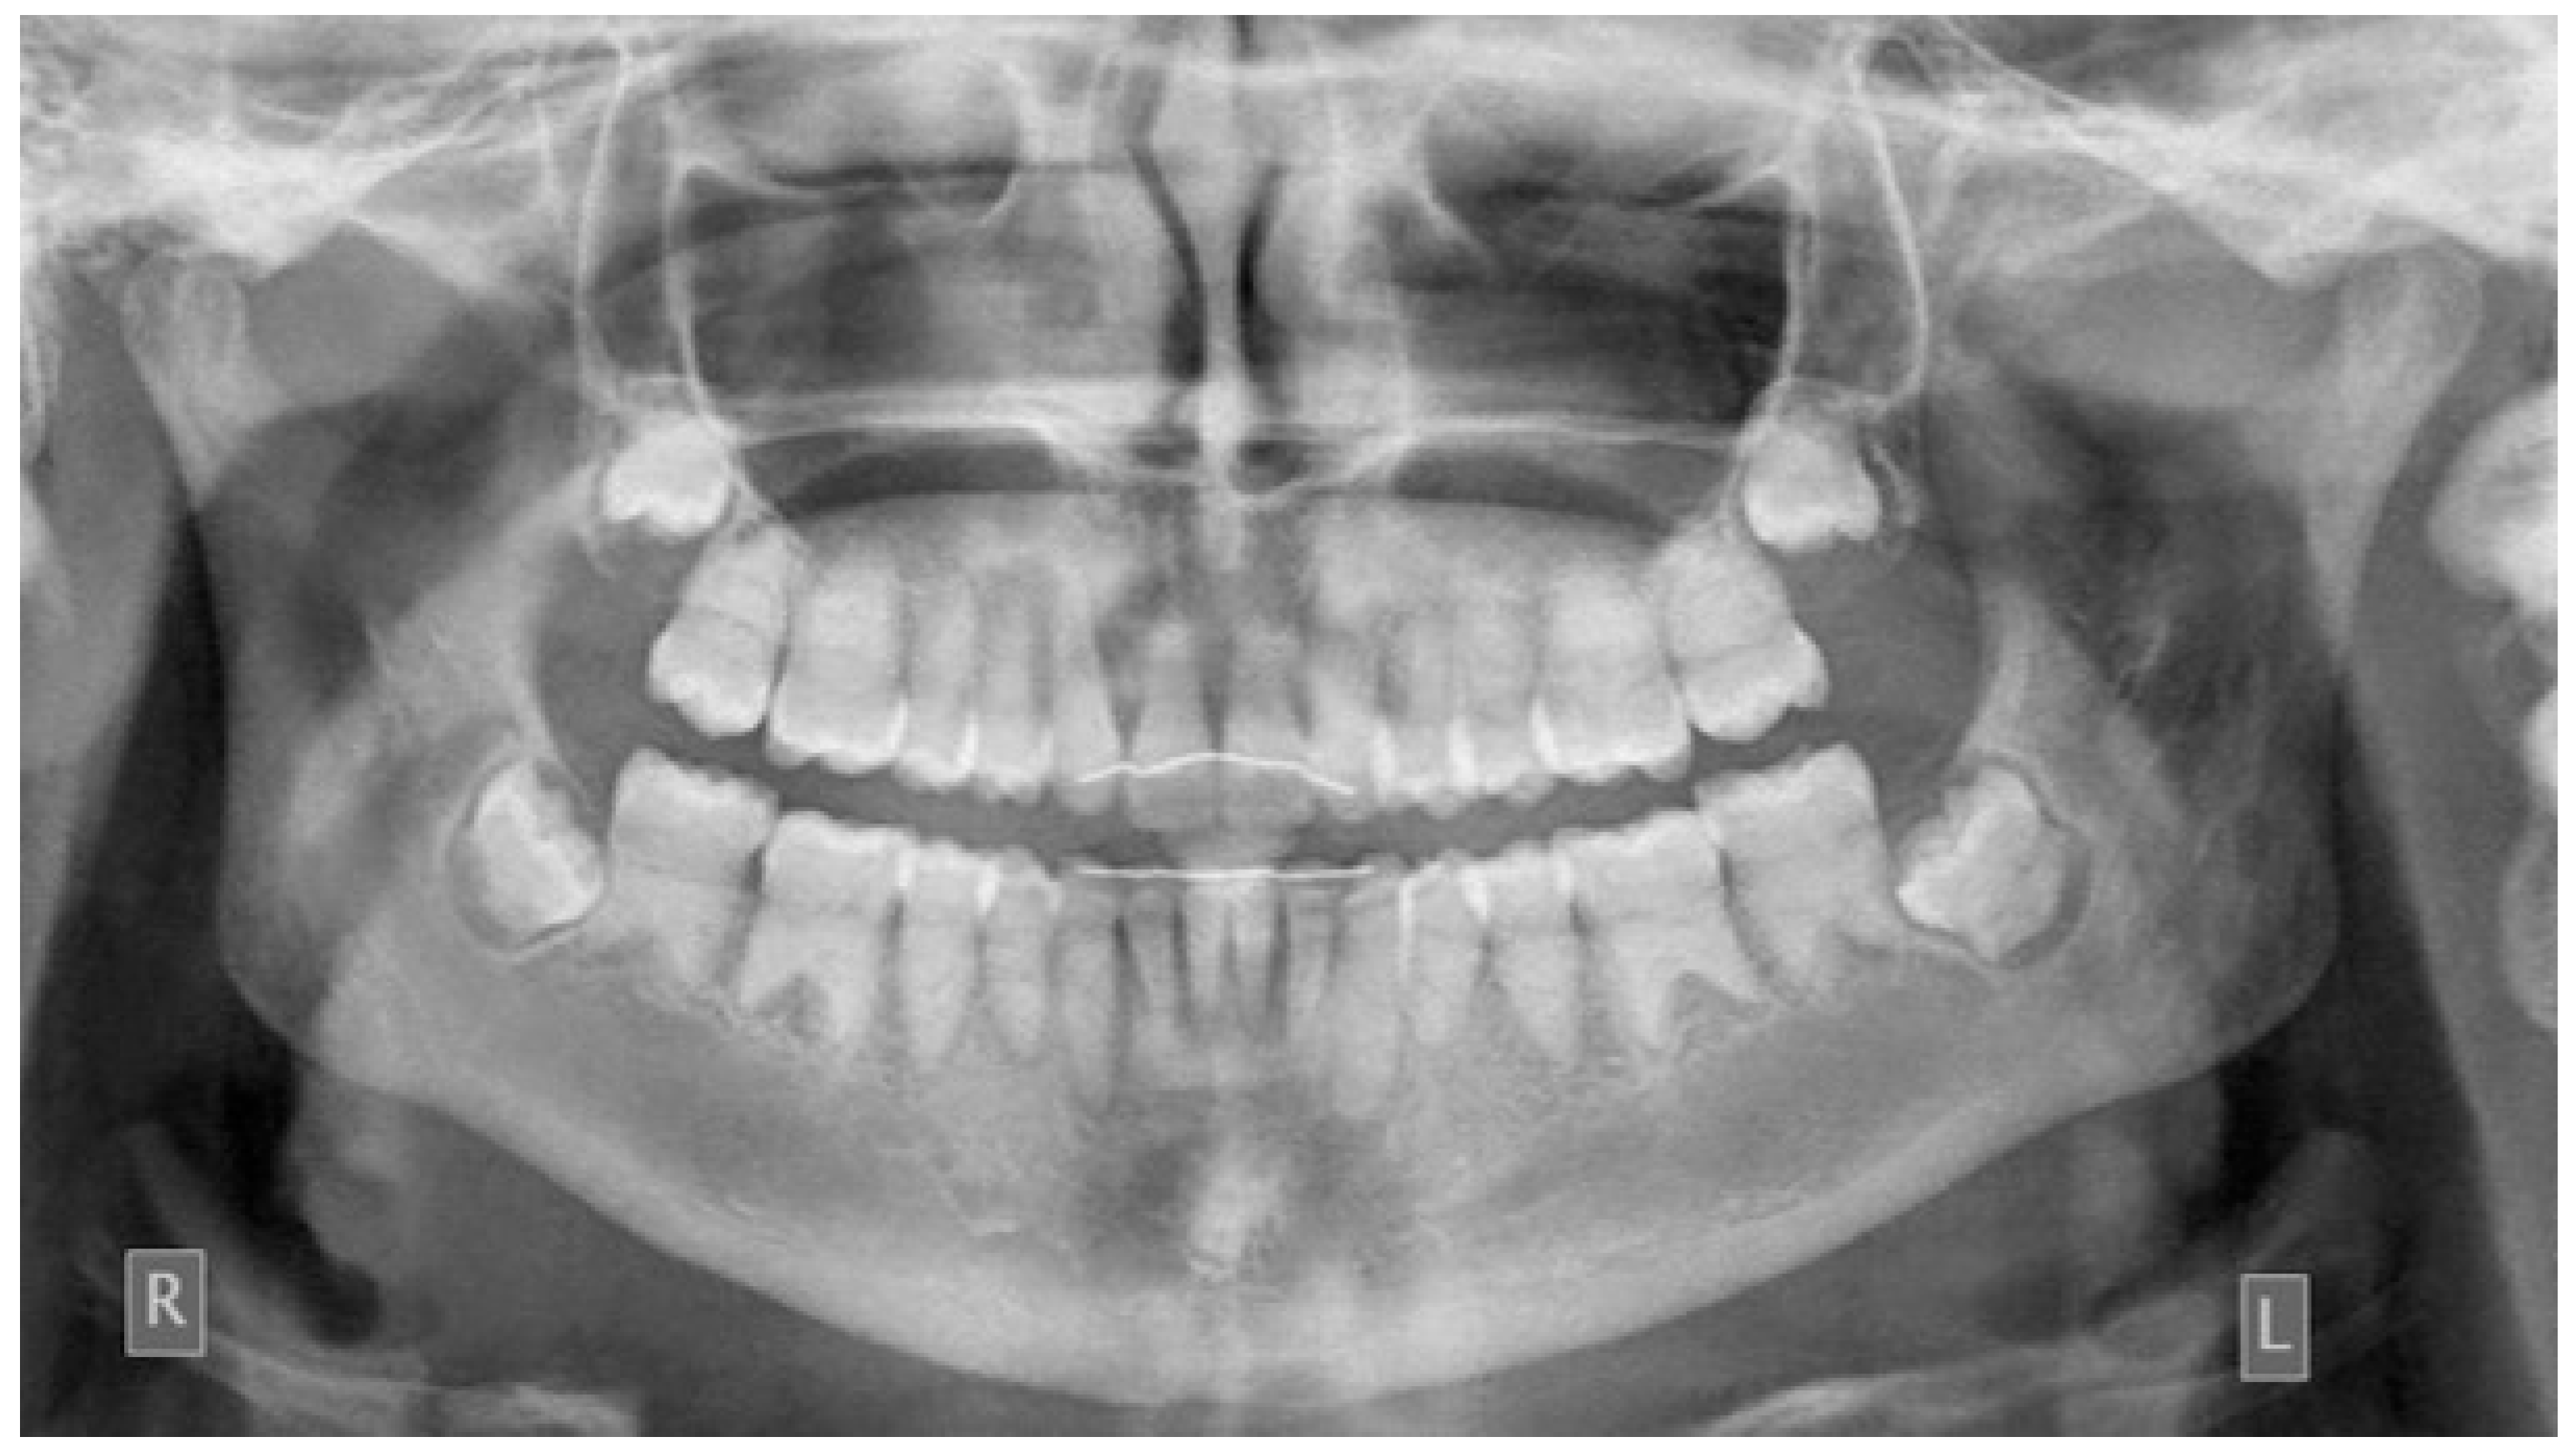

2. Case Presentation

2.1. Clinical Findings and Diagnosis

2.3. Treatment Planning

2.4. Treatment Results